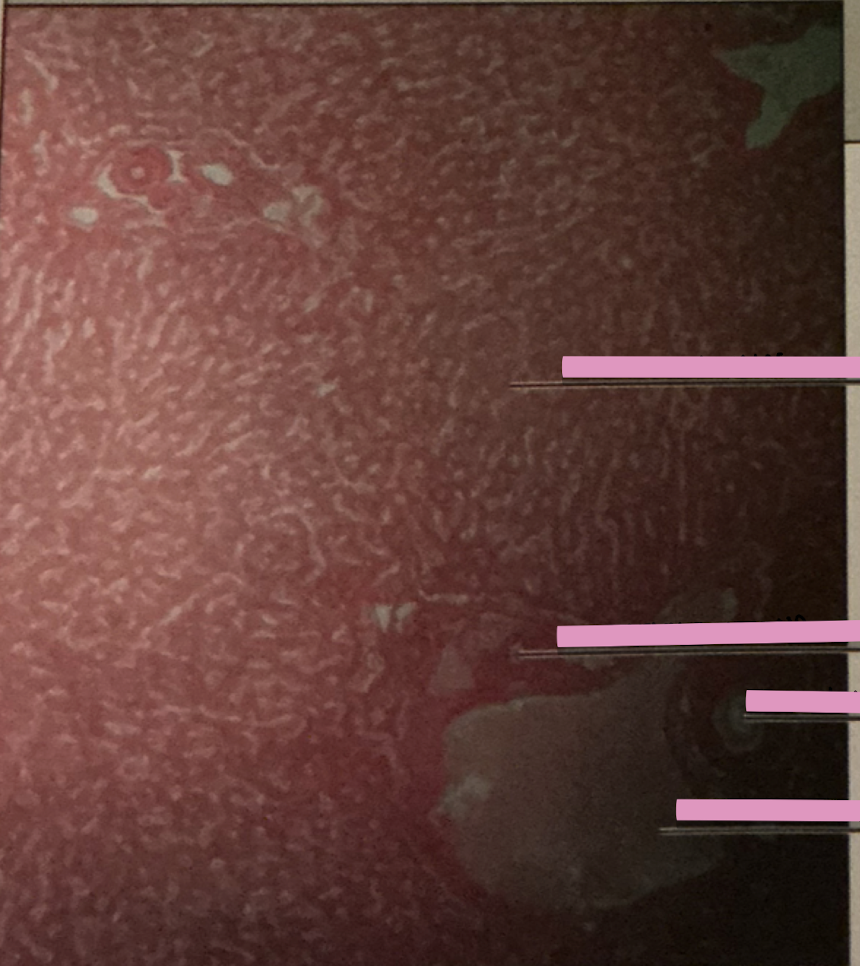

liver

bile duct

hepatocytes

cells that make/secrete blood proteins, store glycogen, release glucose, catabolize drugs & breakdown metabolic products

bile acids

created & —> gallbladder for storage and release; mediate fat digestion

cirrhosis

cirrhosis

disease marked by fibrous fatty deposits in fiber